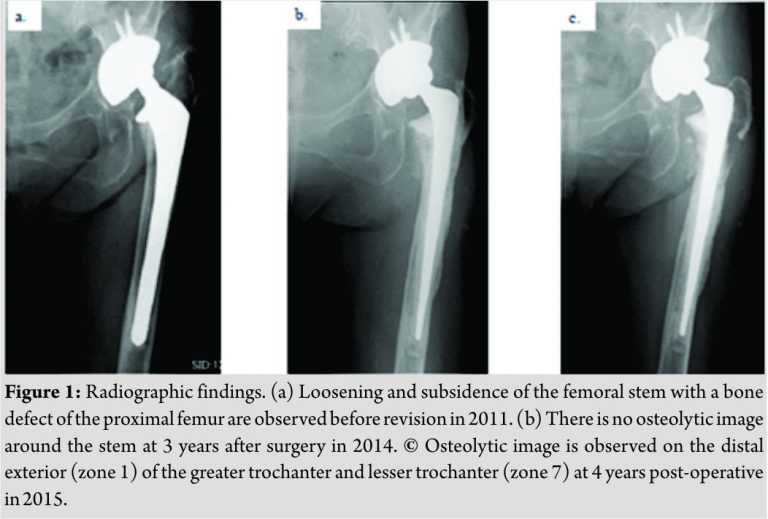

The diameter and neck length of cobalt-chromium metal ball head was 32 and 4 mm, respectively. She was able to leave the hospital without any complications during the perioperative period. Thereafter, there was no obvious abnormal finding on the X-ray and on laboratory investigations until 2014. In 2015, she complained of left hip pain even at rest, without a rise in body temperature. On X-ray, an osteolytic image around the left hip prosthesis was visible, and there was a possibility of urgency fracture at the base of the greater trochanter. She was hospitalized again for examination and treatment. There was no feeling of heat, swelling, or redness around the surgical wound. The range of motion of the left hip joint was as follows: Flexion,90°; extension, 0°; adduction, 20°; abduction, 20°; internal rotation, 10°; and external rotation, 10°. Blood biochemistry showed a white blood cell(WBC) count of 6,040/µL, hemoglobin level of 10.8 g/dL, platelet count of 24,000/µL, C-reaction protein(CRP) level of 0.55 mg/dL, activated partial thromboplastin time of 28.1 s, and prothrombin time international normalized ratio of 1.02.Although there was a mild rise in CRP, the WBC count and fractionation were within normal limits.The harvested synovial fluid was dark red, and the culture was negative. She did not have a history of any oral medications, such as anticoagulants, that could cause easy bleeding. Compared to the X-ray images in 2014, those of 2015 showed an osteolytic image at the distal cortical and cancellous bone of the greater and lesser trochanters, and there was a possibility of imminent fracture at the base of the greater trochanter. Wreckage of HA mesh was found medial to the lesser trochanter (Fig. 1).Onmagnetic resonance imaging (MRI), there was a cystic mass surrounding the prosthesis, which showed a low density on both T1- and T2-weighted images. The inside of the cystic lesion exhibited a mosaic pattern with low- and high-density regions, which spread in a multidirectional manner (Fig. 2). We performed surgery for debridement of the cystic mass and imminent fracture at the base of the greater trochanter. During surgery, a cystic mass with a size of 86 mm×65 mm×58 mm was noted, which was covered with a thick membrane around the hip joint. We punctured it with a syringe, which revealed a reddish brown joint fluid, presumed to be a hematoma. Granulation tissue was observed in the area of osteolysis on the radiograph, and it was confirmed macroscopically that the granules probably generated from the HA mesh were scattered inside(Fig. 3).